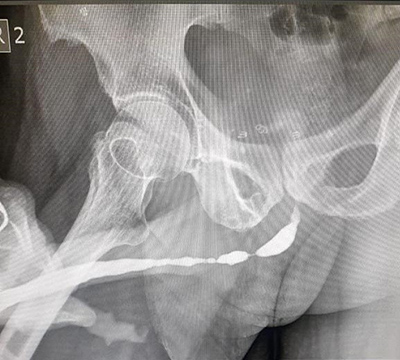

Urethroscopy and Imaging Techniques: Urethroscopy is a technique used to directly examine the urethra. This method provides a detailed view of the internal structure of the urethra. Additionally, imaging techniques such as ultrasound and MRI can be used in diagnosis. These techniques help determine the location and size of the urethral stricture.